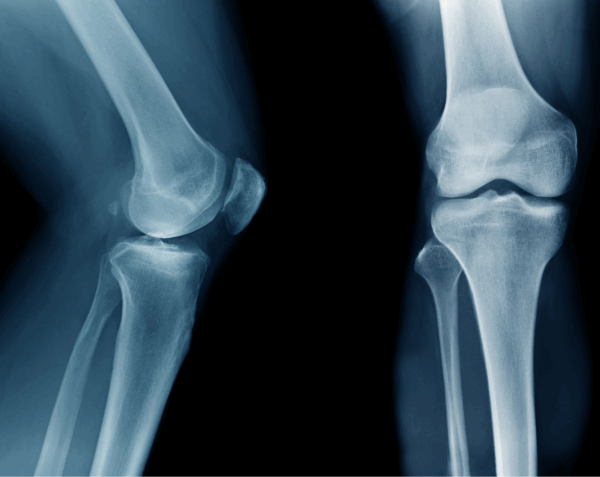

A right knee X-ray produces detailed images of the knee joint, including the femur, tibia, fibula, and patella. Physicians often order this test to evaluate injuries, detect arthritis, monitor post-surgical healing, or investigate persistent joint pain. At Desert Mobile Medical, we bring hospital-grade mobile X-ray technology directly to you—so you get accurate results quickly, privately, and without the hassle of urgent care or hospital visits.

Injury or Trauma – To check for fractures after falls, accidents, or sports injuries.

Chronic Knee Pain – To detect arthritis, bone spurs, or degenerative joint changes.

Possible Dislocation – To confirm alignment of the knee joint.

Because it is quick, safe, and reliable, a knee X-ray often serves as the first step in diagnosis before advanced imaging such as MRI or CT.